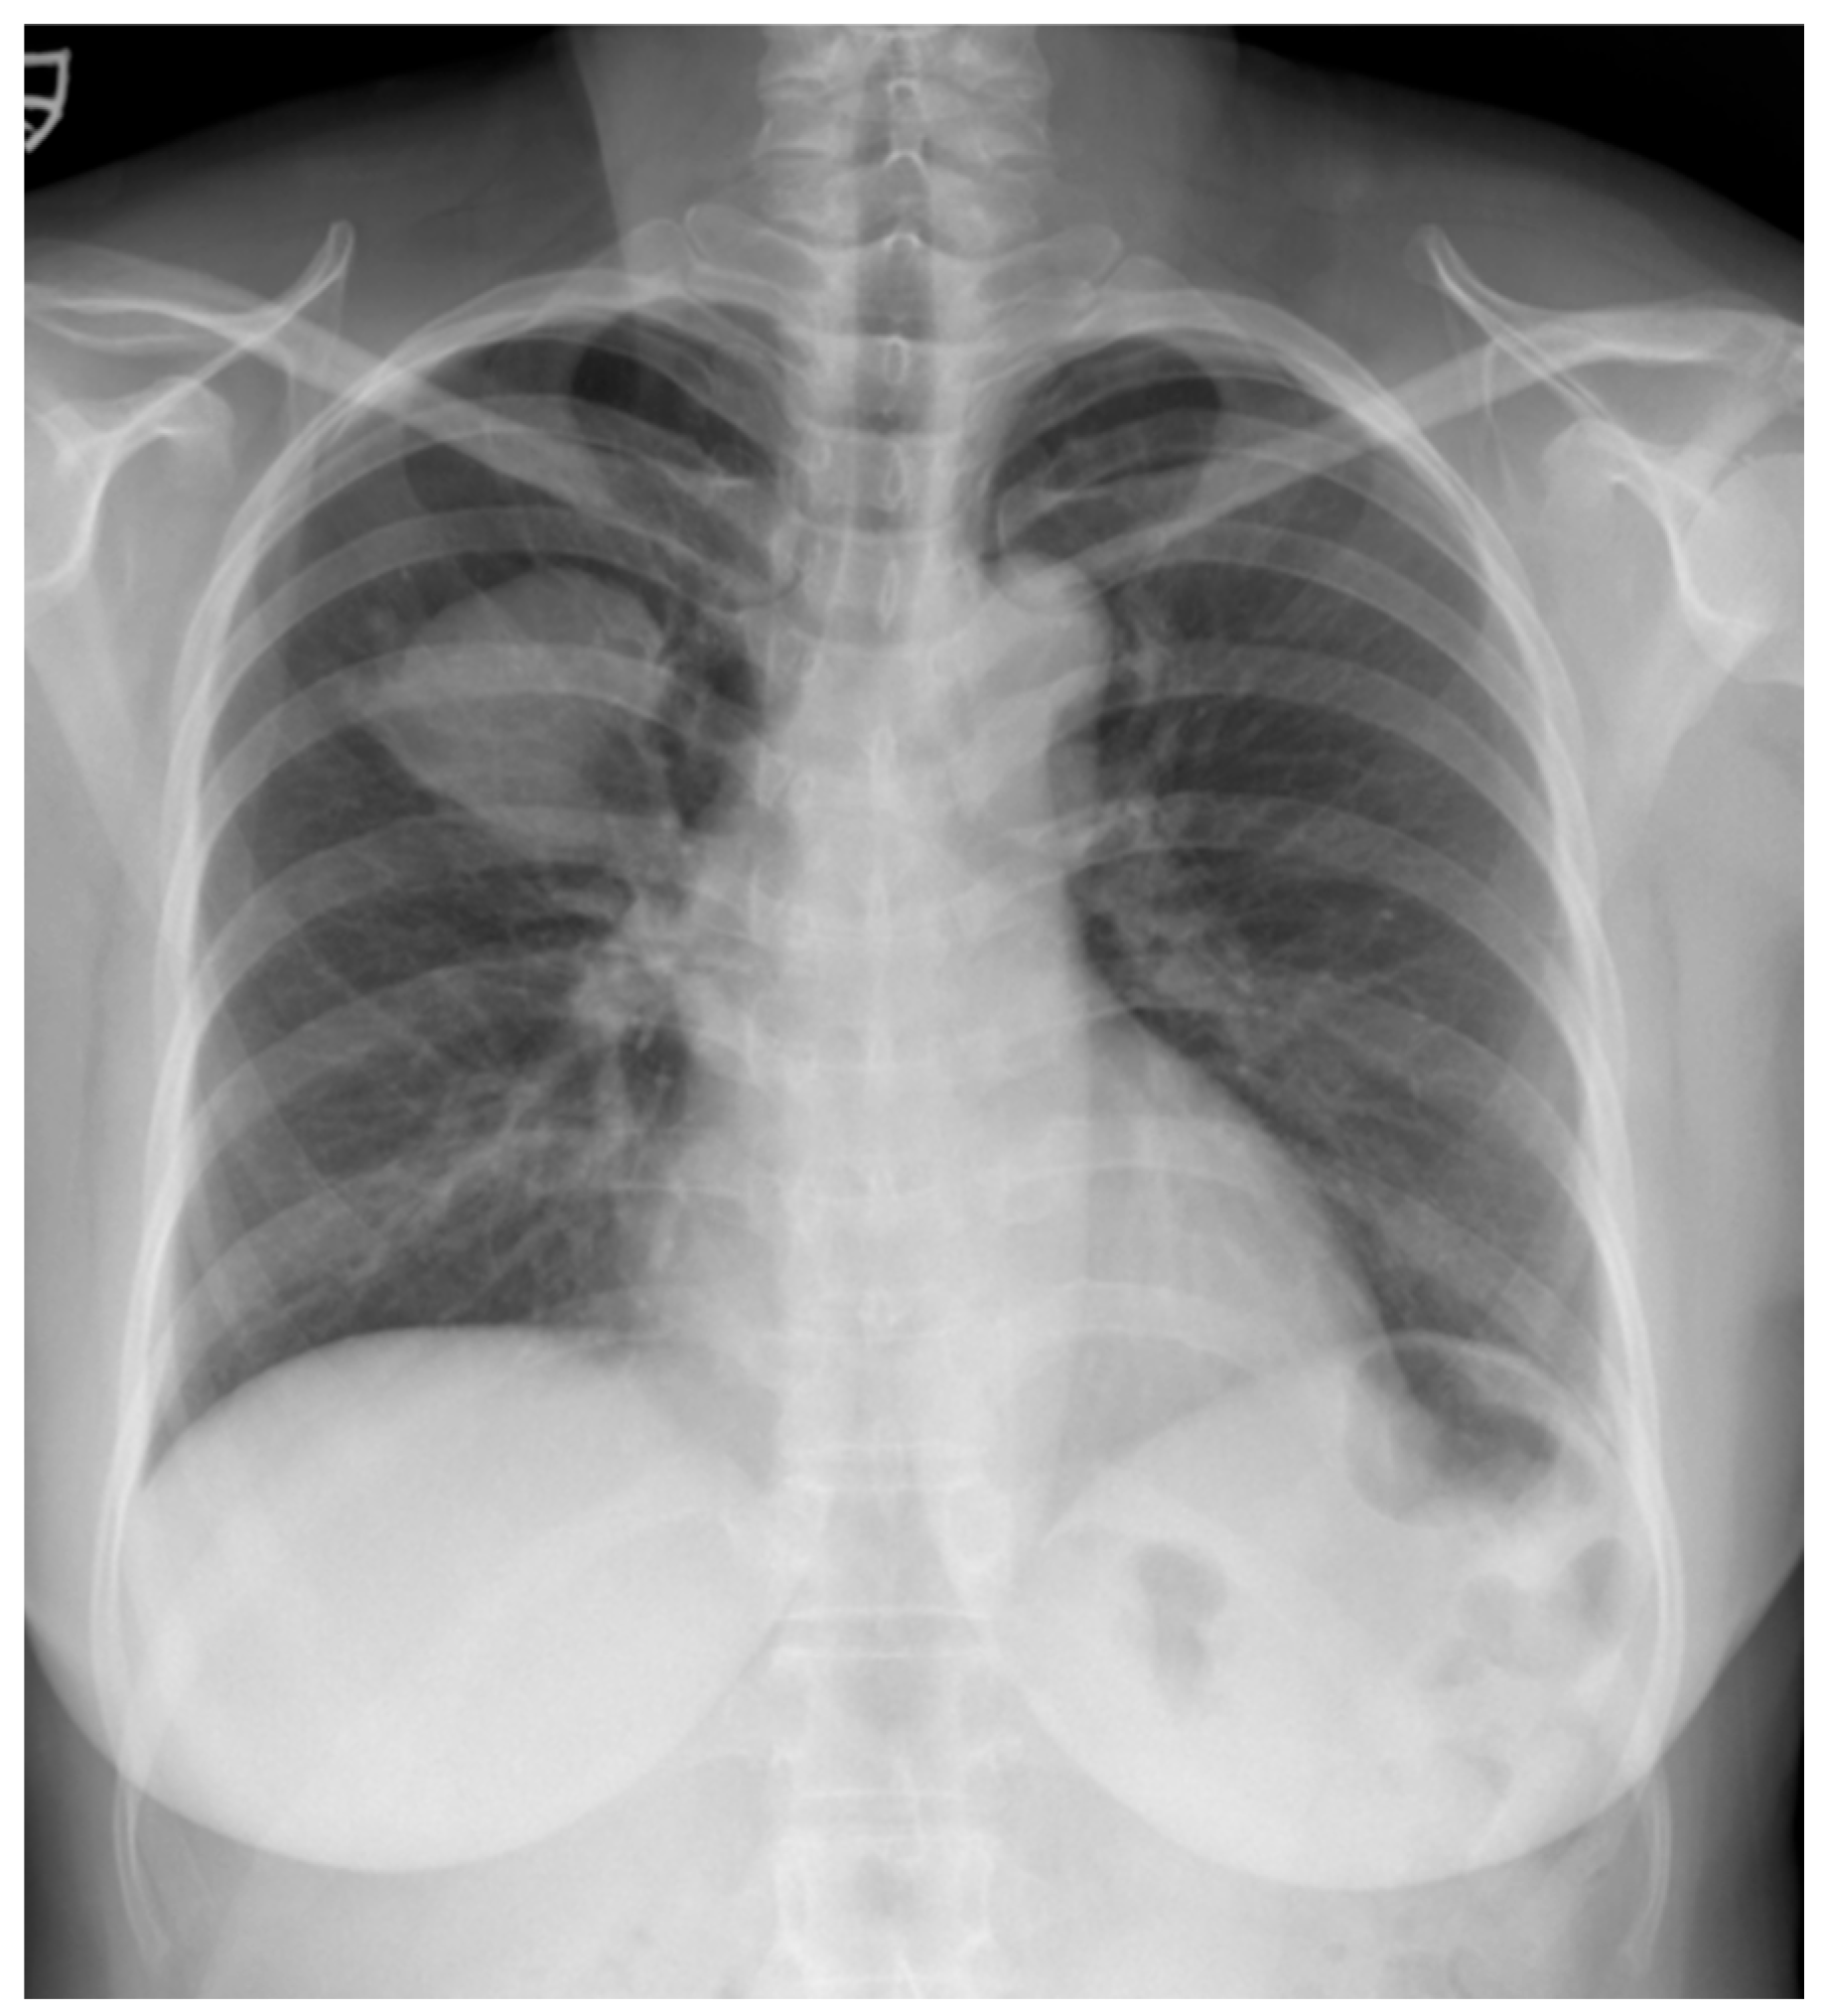

A 52-year-old woman was admitted to our hospital with a three-month history of cough and sputum, along with a one-month history of hemoptysis. Her medical history was unremarkable, and she was a nonsmoker. The laboratory results were within normal limits. Chest radiography revealed a well-defined mass-like opacity with a partially lobulated lateral edge in the right upper zone (Figure 1). Unenhanced CT showed a homogeneous hypodense mass (Hounsfield Unit: 20) measuring approximately 56 × 44 × 42 mm in diameter, with well-defined, mostly smooth, but partially lobulated margins in the right upper lobe (Figure 2a). The mass effect caused splaying of the anterior and posterior segmental bronchi, unlike bronchial obstruction typically observed in lung cancer (Figure 2b). Contrast-enhanced CT (CECT) revealed a predominantly poorly enhancing mass resembling a cystic lesion with a small but strong nodular or curvilinear peripheral enhancement (Figure 3). No mediastinal adenopathy was observed.

Figure 1.

A chest radiograph at the initial visit showed a well-defined mass-like opacity with a partially lobulated lateral edge in the right upper zone.